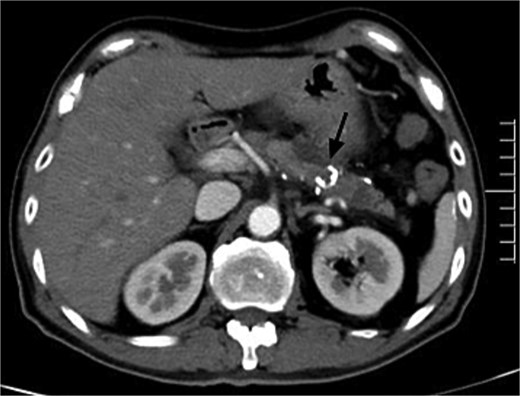

A 45-year-old man with upper abdominal pain for 3 days was referred to our unit. His past history was unremarkable. Upon physical examination, He had abdominal tenderness. Routine blood test showed elevated amylase and lipase (395.8 and 536.7 U/l). Enhanced computed tomography (CT) demonstrated tortuous dilated arteries in the pancreas body and tail with a small pseudocyst, and early opacification of the portal vein, but no signs of portal hypertension (Fig. 1). Endoscopy revealed no varices and ulcers. Based on these findings, a diagnosis of PVAM with AP was made.

Enhanced CT showed tortuous dilated arteries in the pancreas body and tail (black arrow) with a small pseudocyst (red arrow) and early opacification of the splenic vein and portal vein (white arrows).